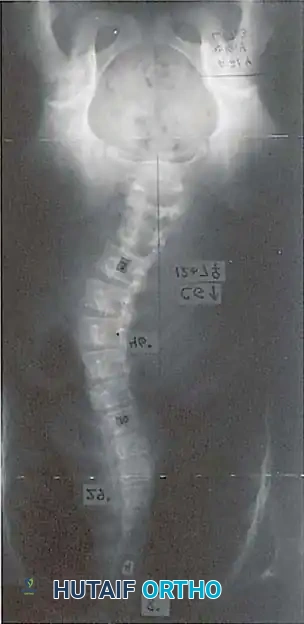

The concept of concave rib osteotomies as a structural release procedure for severe spinal deformity was first introduced by Flinchum in 1963. Subsequently, prominent deformity surgeons including Kostuik, Tolo, Goldstein, and Mann et al. expanded upon its utility, demonstrating its value in mobilizing rigid thoracic and thoracolumbar curves.

The biomechanical rationale for this procedure is rooted in the tension-band effect of the thoracic cage. In severe scoliosis, the ribs on the concave side of the curve become structurally contracted, acting as a rigid tether that resists coronal correction and derotation. Halsall et al. conducted pivotal cadaveric studies testing spinal flexibility before and after the sectioning of ribs on the tension (concave) side. Their findings demonstrated an average increase in coronal deflection of 53%, with the maximum increase in flexibility achieved when five or six apical ribs were resected or osteotomized.

Indications and Curve Selection

The ideal candidate for an anterior approach is a patient with a Lenke Type 4 curve pattern, where the thoracolumbar or lumbar curve is the primary structural component, and the main thoracic or proximal thoracic curves are nonstructural and highly flexible.

Radiographic Prerequisites

Careful preoperative radiographic analysis is mandatory:

1. Flexibility: The thoracolumbar or lumbar curve must demonstrate significant flexibility on side-bending films.

2. Thoracic Curve: The compensatory thoracic curve must be nonstructural, reducing to 25 degrees or less on supine bending films.

3. Fractional Curve: The incomplete (fractional) curve between the lowest instrumented vertebra (LIV) and the sacrum must be carefully evaluated. It must be flexible enough to correct and become horizontal on bending films.